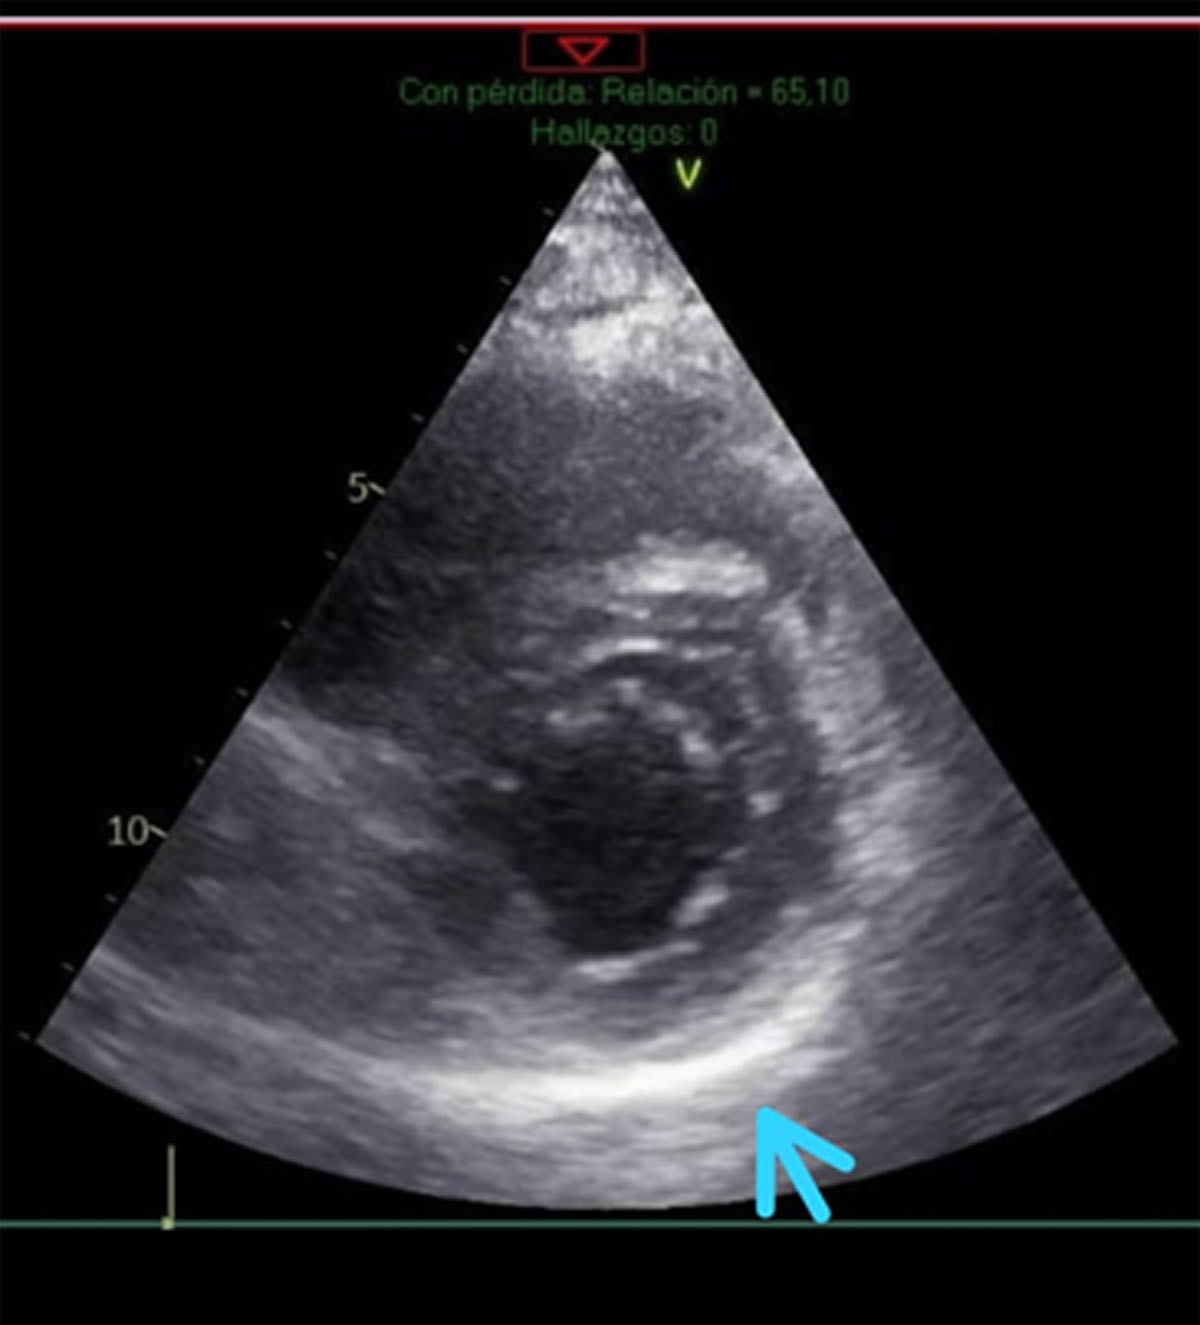

Figure 2

Echocardiogram of the short axis with thickening of the parietal pericardium.